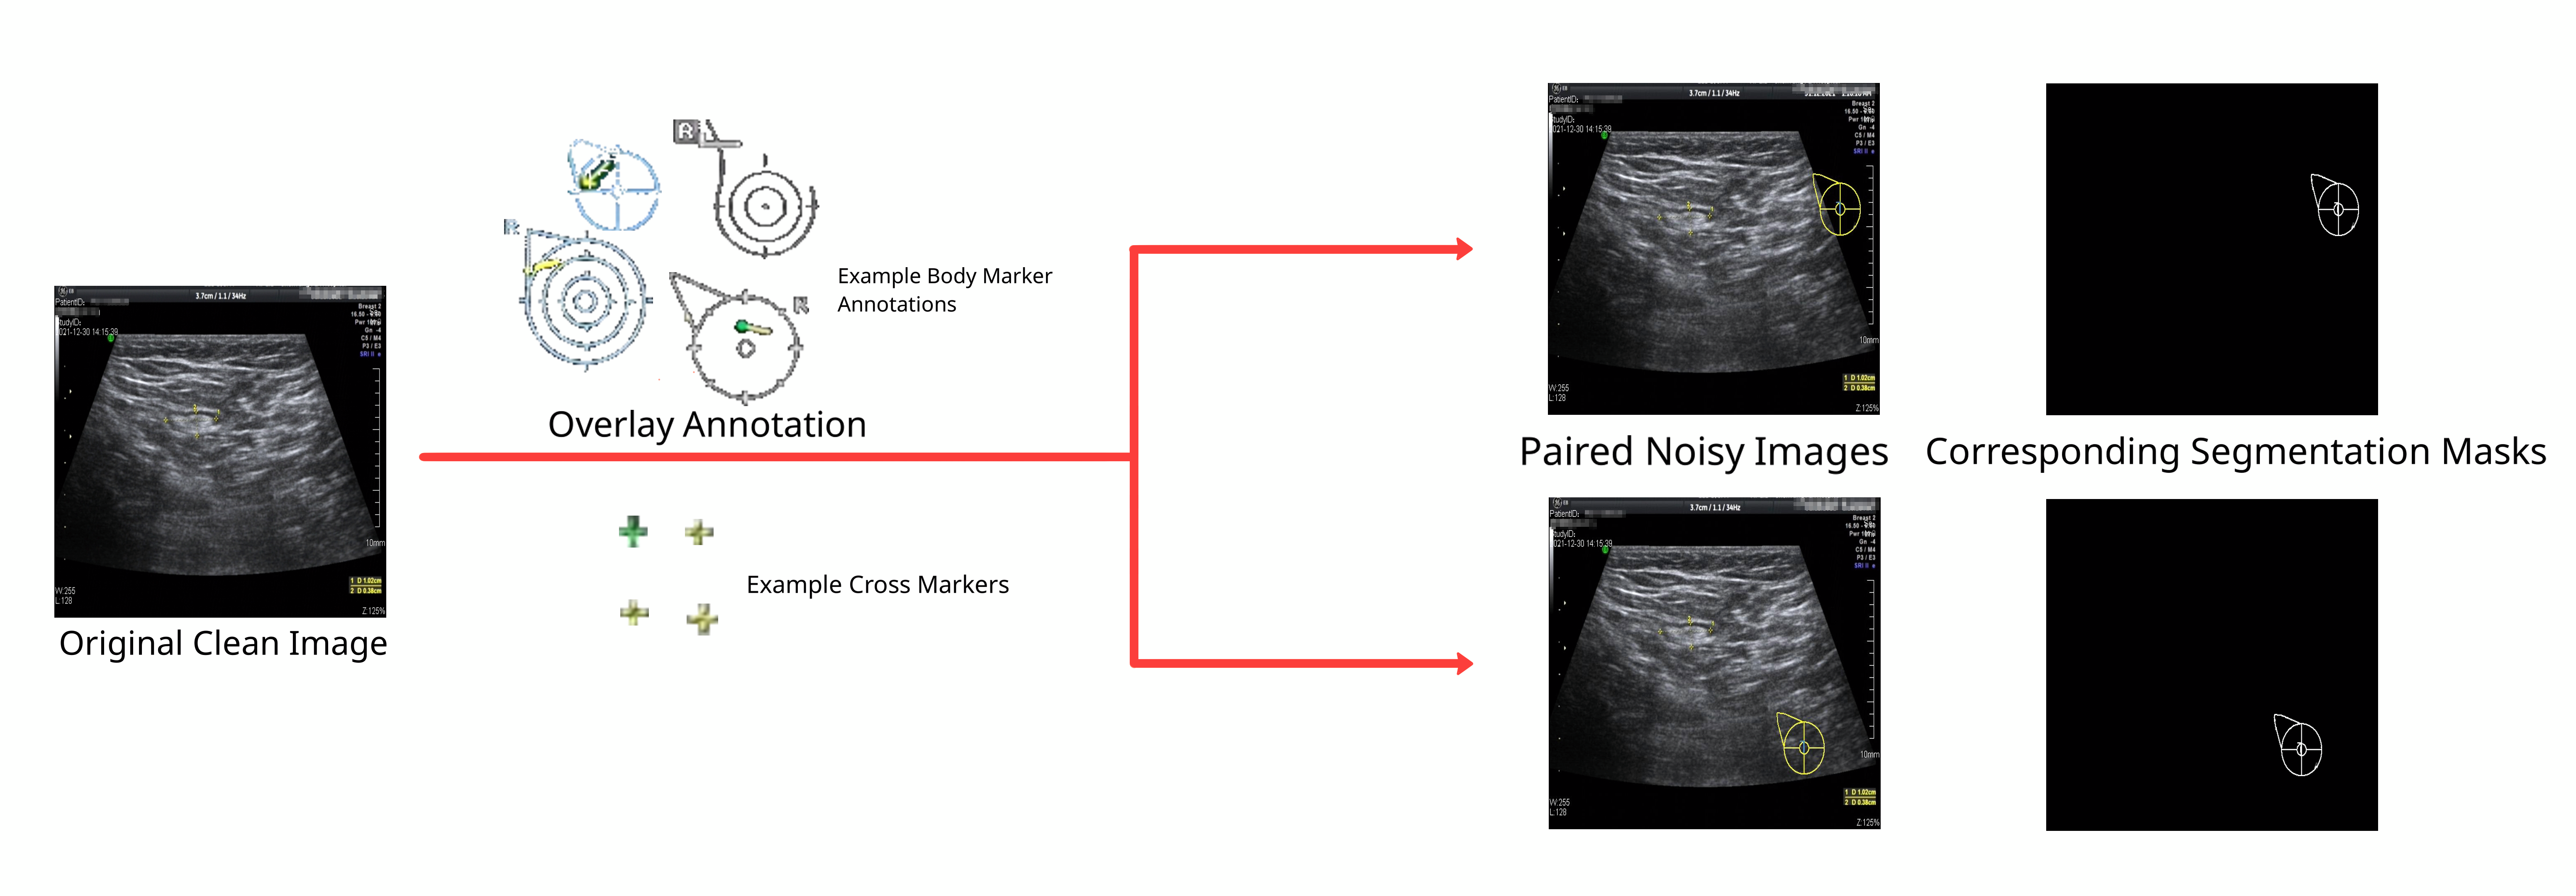

To synthesize a Noise2Noise training dataset for above annotations, we first manually extracted the necessary annotation icons from existing annotated data, then we randomly overlay different annotations on the clean images we have. The randomness of the noise overlay allows for the creation of a relatively large dataset.

By constructing training datasets in the above-mentioned process, each noisy image has three corresponding images for different tasks.

• A clean image which the noisy image originated from.

• A different noisy image created from the same clean image, using a different (in terms of position, form, etc.) noise sampled from the same distribution.

• A binary image recorded the position and form of the noise appended to the clean image.

An instance of the training dataset is presented in Fig. 2. Using these images, the same dataset can be used for Noise2Noise training, conventional Noise2Clean training, and normal segmentation training.

Our approach to create this training dataset can minimize the amount of human labor required. Even with a limited amount of clean data, we are able to generate a large noisy dataset for training. The flow chart of the above process is also shown in Fig. 2.

Figure 2: Flow Chart of Training Dataset Building